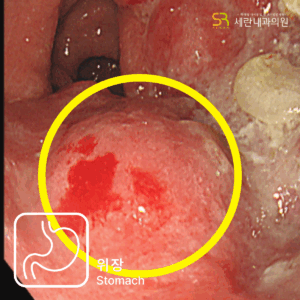

가스 차는 증상과 경미한 혈변으로 발견된 직장암 사례설사와 혈변, 항문 통증으로 내원했다가 직장암을 진단받은 40대 남성 사례심한 변비로 내원하여 상행결장암을 진단받은 80대 남성 사례속쓰림으로 내원했다가 복부초음파로 조기 담낭암을 발견한 사례명치 통증과 소화불량으로 내원했다가 췌장암 3기가 진단된 사례무증상 검진 중 갑상선초음파로 발견된 조기 갑상선 유두암 사례유방 통증으로 내원했다가 유방초음파로 조기 진단된 침윤성 유방암 사례명치 통증으로 내원했다가 진행성 위암을 발견한 60대 여성 사례속쓰림으로 내원했다가 signet ring cell type 위암을 조기 발견한 60대 여성 사례소화불량으로 내원했다가 작은 조기 위선암을 발견한 50대 여성 사례변비로 내원했다가 침윤성 궤양 형태의 위암을 발견한 70대 여성 사례소화불량으로 내원했다가 진행성 위암을 발견한 60대 여성 사례경미한 속쓰림으로 방문했다가 조기 위선암을 발견한 60대 여성 사례가스 차는 증상과 경미한 혈변으로 발견된 직장암 사례설사와 혈변, 항문 통증으로 내원했다가 직장암을 진단받은 40대 남성 사례심한 변비로 내원하여 상행결장암을 진단받은 80대 남성 사례속쓰림으로 내원했다가 복부초음파로 조기 담낭암을 발견한 사례명치 통증과 소화불량으로 내원했다가 췌장암 3기가 진단된 사례무증상 검진 중 갑상선초음파로 발견된 조기 갑상선 유두암 사례유방 통증으로 내원했다가 유방초음파로 조기 진단된 침윤성 유방암 사례명치 통증으로 내원했다가 진행성 위암을 발견한 60대 여성 사례속쓰림으로 내원했다가 signet ring cell type 위암을 조기 발견한 60대 여성 사례소화불량으로 내원했다가 작은 조기 위선암을 발견한 50대 여성 사례변비로 내원했다가 침윤성 궤양 형태의 위암을 발견한 70대 여성 사례소화불량으로 내원했다가 진행성 위암을 발견한 60대 여성 사례경미한 속쓰림으로 방문했다가 조기 위선암을 발견한 60대 여성 사례

10만례 이상의 내시경 경험,

세란의 정확한 진단

내과 · 소화기내시경세부 전문의가

직접 시행하는 위 · 대장내시경

100,000례 이상의 풍부한 임상 경험과

대학병원급 장비로 세란내과의원은

정확한 진단과 안전한 검사를 제공합니다.